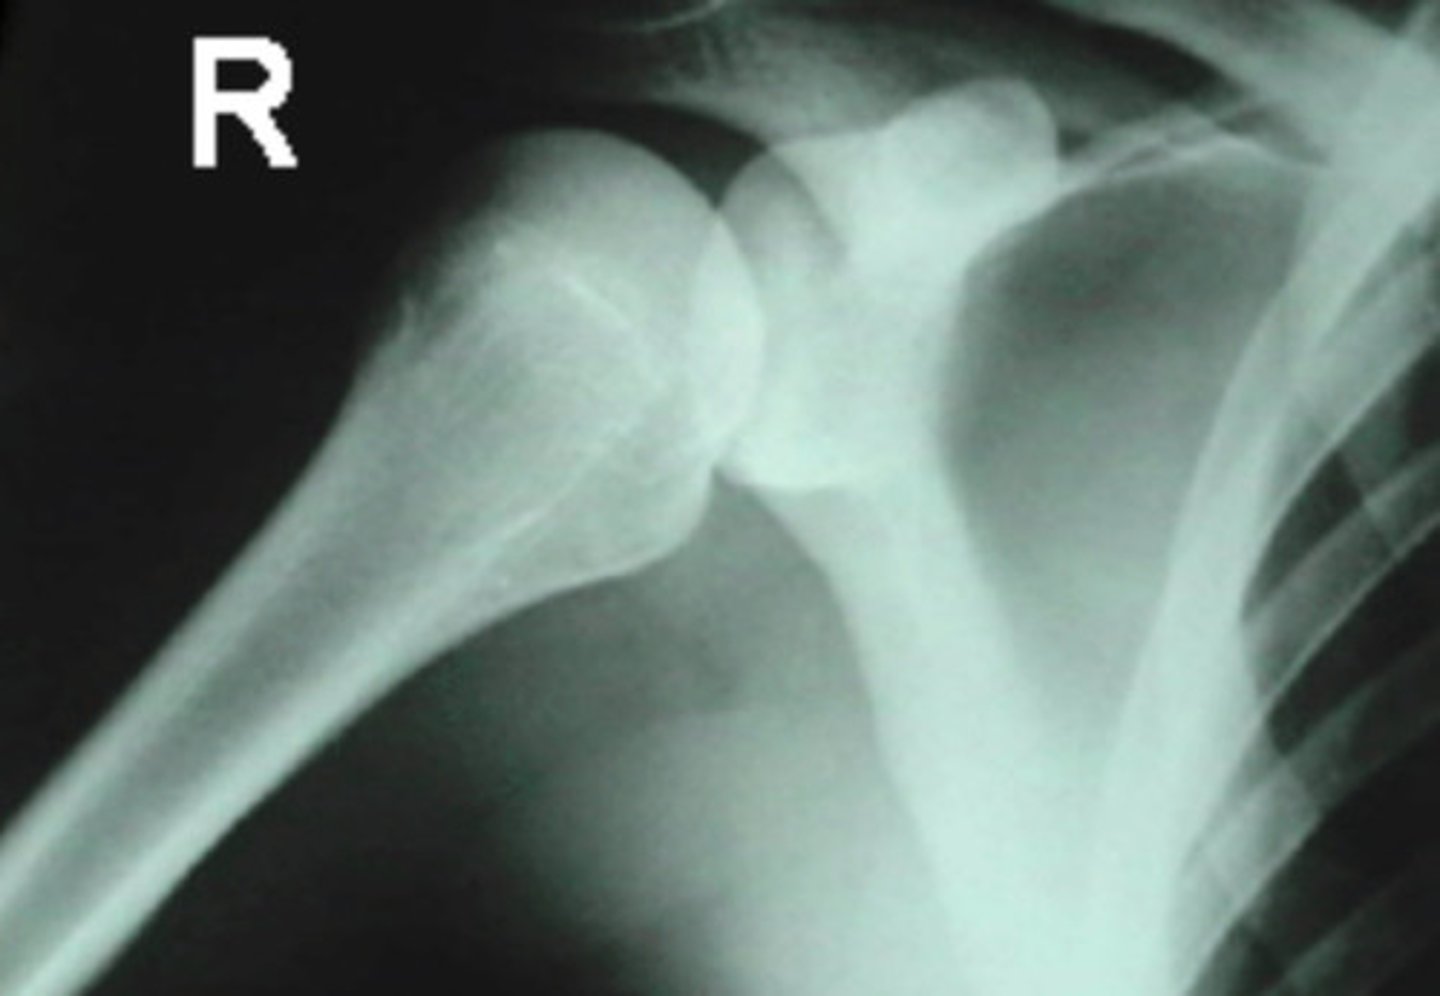

AP Internal Rotation of Shoulder

What is the name of the radiographic projection seen here?

AP External Rotation of Shoulder

What radiographic projection is the Acromiohumeral joint assessed upon?